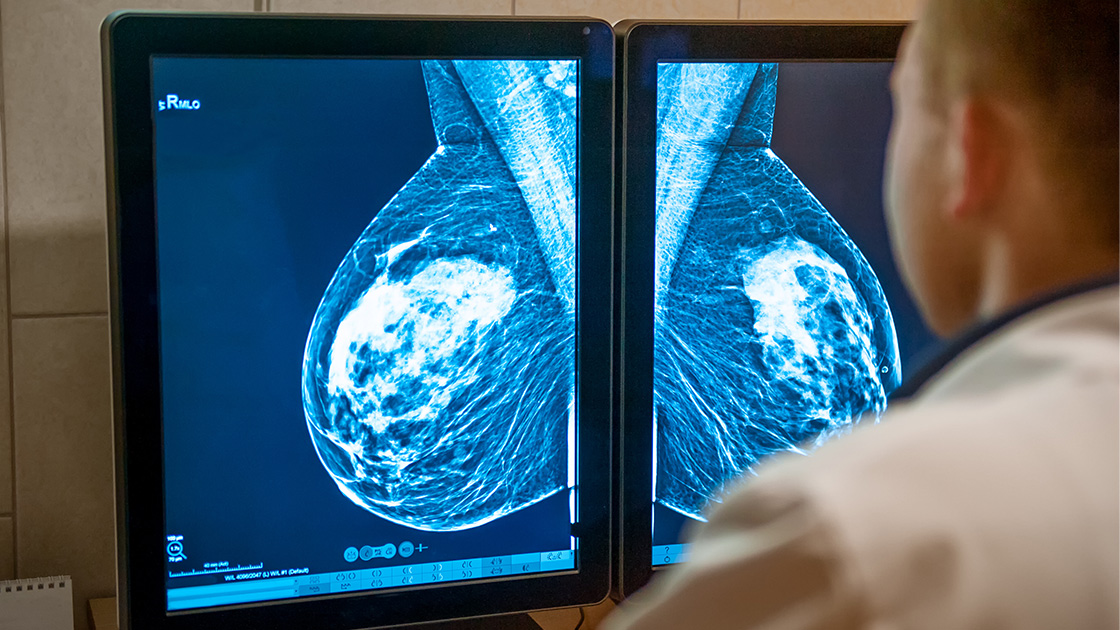

Waar een borstamputatie vroeger onvermijdelijk gepaard ging met zichtbare littekens, biedt een nieuwe techniek vandaag uitzicht op een minder ingrijpende aanpak mét behoud van esthetiek. Dr. Femke Delporte, gynaecologe en medisch coördinator van de Borstkliniek bij AZ Sint-Lucas Brugge, licht toe hoe de endoscopische tepelsparende mastectomie (E-NSM) het verschil maakt.

“Een klassieke borstamputatie is een zichtbaar verminkende ingreep”, legt Dr. Delporte uit. “Hoewel technieken met secundaire reconstructie en conventionele huidsparende en tepelsparende mastectomie met directe reconstructie een belangrijke esthetische vooruitgang betekenden, blijft de emotionele en psychologische impact van een mastectomie voor patiënten groot.”

“Met de komst van de endoscopische tepelsparende mastectomie kunnen we nog net iets verder gaan en wordt het litteken quasi onzichtbaar. We werken dan via een kleine incisie in de oksel. Met behulp van een endoscoop kunnen we het borstklierweefsel zorgvuldig verwijderen, terwijl de huid en de tepel volledig behouden blijven.”

Dr. Delporte: “Dankzij het sterk vergrote beeld en de ergonomische werkwijze kan ik zeer nauwkeurig opereren. We kunnen aansluitend meteen een reconstructie uitvoeren, waarbij door dezelfde kleine incisie een prothese wordt geplaatst. Voor de patiënte betekent dat een natuurlijker resultaat en minder zichtbare littekens.”

Hoewel het om een complexere kijkoperatie gaat, is de veiligheid minstens vergelijkbaar met de klassieke methode. “De overlevingscijfers zijn gelijkaardig. Bovendien zien we minder complicaties en minder postoperatieve pijn.” De juiste opleiding is daarbij cruciaal. Dr. Delporte volgde een gespecialiseerde training bij Applied Medical in Amsterdam, onder begeleiding van internationale experts. “Die training is wenselijk om deze techniek veilig aan te bieden.”

Niet elke patiënte komt automatisch in aanmerking voor E-NSM. “Voor vrouwen met een hoog genetisch risico op borstkanker kan deze techniek ideaal zijn om het risico preventief te verlagen, met behoud van esthetiek”, zegt Dr. Delporte. “Maar factoren zoals cupmaat en borstvorm spelen een belangrijke rol.”

Wanneer er al borstkanker aanwezig is, gelden bijkomende veiligheidscriteria. “Er moet voldoende afstand zijn tussen de tumor en de tepel en huid. Dat bespreken we altijd multidisciplinair én samen met de patiënte. Ook de keuze van de reconstructie en het type prothese bekijken we in overleg.”